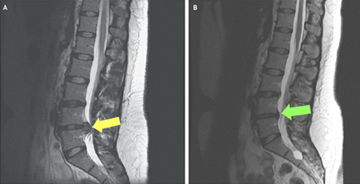

If a herniated disc is suspected, imaging may be used to confirm the diagnosis and assess its severity:

- Magnetic resonance imaging (MRI) – MRI scans provide clear images of soft tissues, including discs and nerves, and are the most common test used to confirm a disc herniation.